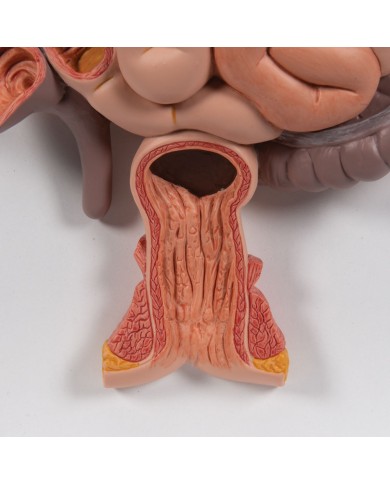

I Modelli anatomici 3B scientific ed Erler Zimmer sono quanto di meglio esista per studiare l'anatomia del corpo umano, il catalogo dei modelli anatomici comprende modelli di cranio, scomponibili, colorati, crani anatomici, crani su cavalletto, e il modello di punta, il cranio in 22 parti, ad incastro magnetico.

Questo e tanto altro ancora trovi nella sezione dedicata ai modellini anatomici, occhi, denti, orecchio, naso e gola, e i modelli anatomici per ostetricia e ginecologia, per lo studio dell'anatomia della pelvi e del bacino umano.

I modelli anatomici didattici sono riproduzioni di strutture anatomiche perfettamente uguali a quelle vere, i modelli di ossa sono realizzati dalla scansione di ossa vere, l'esperienza tattile è assolutamente realistica, ed anche il peso delle ossa corrisponde all'incirca al peso delle ossa vere.

Sono indispensabili per lo studio dell'anatomia umana, oggi è possibile osservare le strutture anatomiche senza la necessità di dissezionare cadaveri o di effettuare studi pericolosi su pazienti vivi.

Gli studenti di medicina utilizzano i modelli anatomici per i loro studi di anatomia umana, studiare l'anatomia sui libri non basta, un modellino anatomico permette uno studio molto più accurato che una foto o un disegno su un libro.

Medici, fisioterapisti, osteopati e professionisti sanitari utilizzano i modelli anatomici per dare spiegazioni ai pazienti sulle patologie, risparmiando tanto tempo prezioso durante la spiegazione, che diventa molto più efficace.